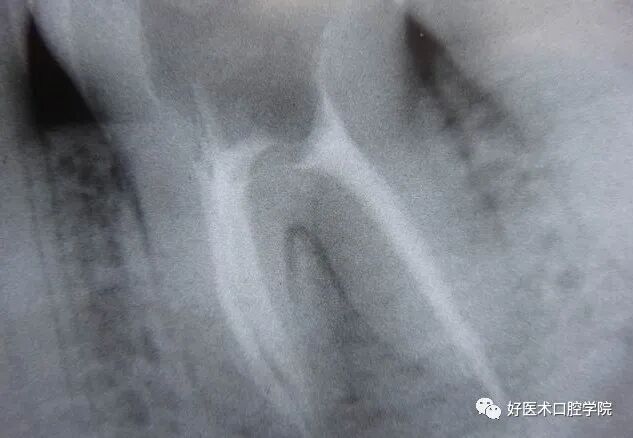

根分叉疾病:

非专业的牙周病科医生一般遇到根分叉疾病,根分叉处X光上有阴影的,都认为很难治疗好患牙。为了不给自己找麻烦往往接诊后直接就给予拔除。其实这样处理是不合适的,绝大多数单纯的根分叉疾病通过洁治和刮治根分叉区域后定期按疗程上派力奥就可以痊愈,为患者保留了患牙。